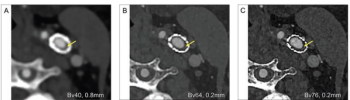

Researchers found that ultra-high resolution photon-counting significantly enhanced visualization of small vessels and facilitated improved reduction of blooming artifacts for head and neck computed tomography angiography (CTA) scans.